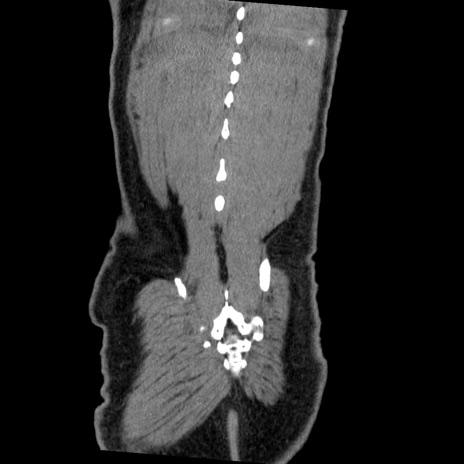

症例22(冠状断像)

【症例】50歳代男性

【主訴】腹痛

【現病歴】AVMからの被殻出血のため回復期リハ病棟入院中。 本日午後3時頃急に下腹部痛が出現した。

【既往歴】AVM、被殻出血、虫垂炎、高血圧

【身体所見】意識晴明、左半身不全麻痺、会話の理解は良好、36.5°C、腹部:膨隆、全体に板状硬、下腹部正中に圧痛点あり、反跳痛-、筋性防御不明、右下腹部にope scar

【データ】WBC 9400、CRP 0.06